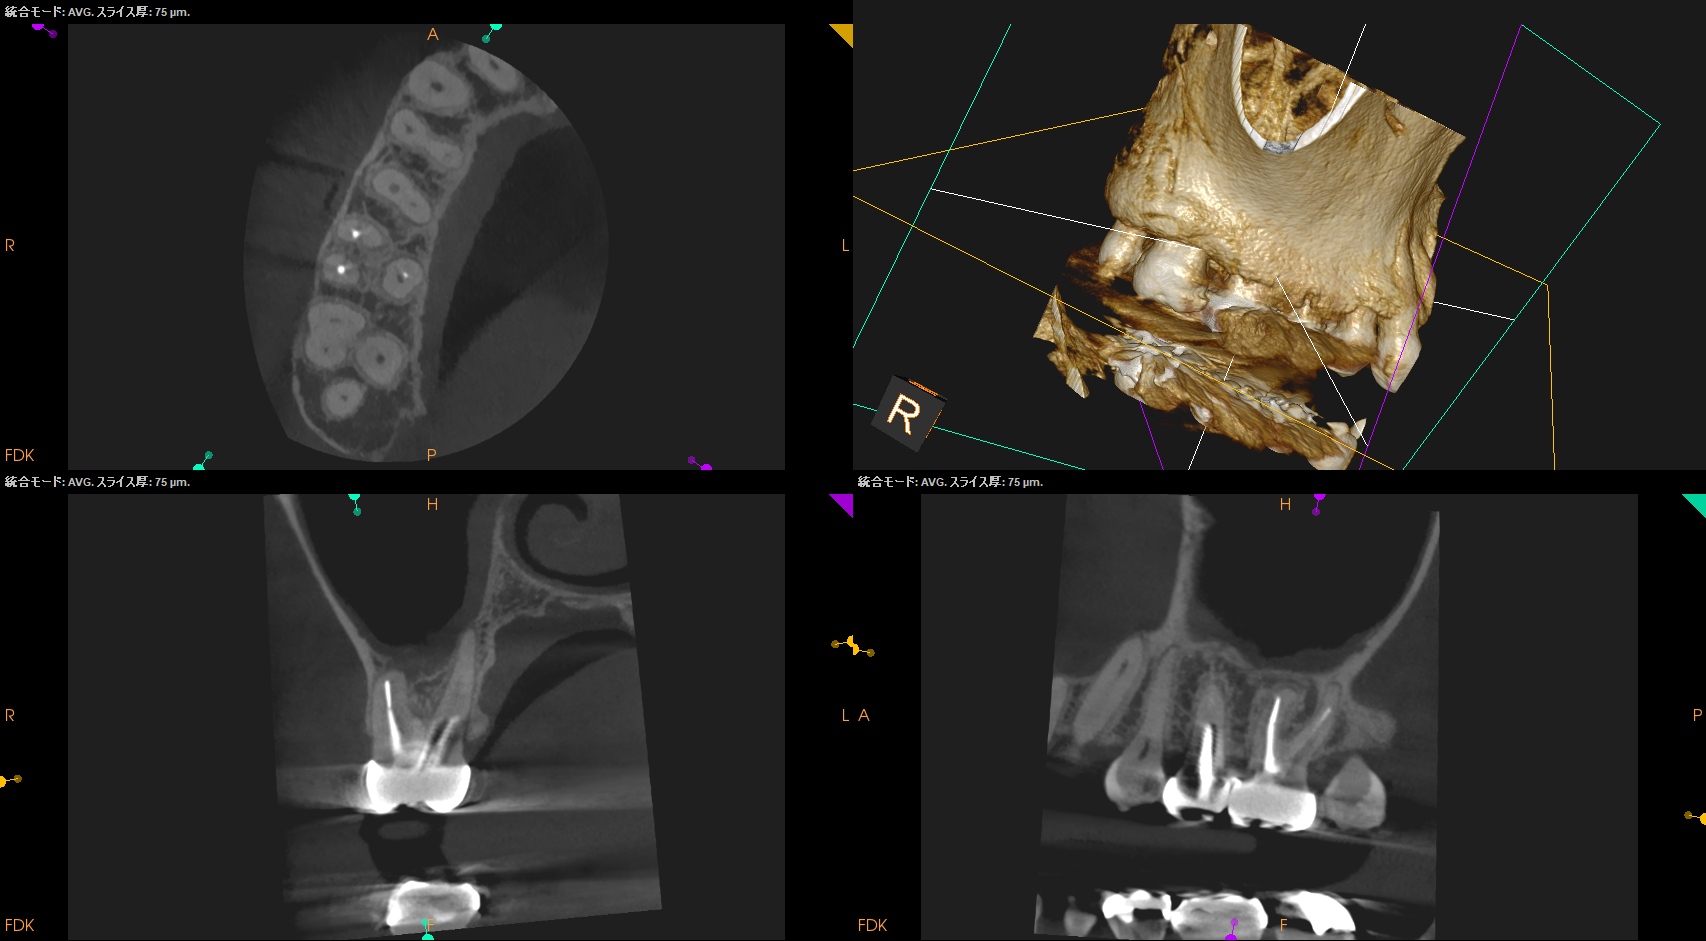

CBCT(2025.9.1)

#3

MB

DB

P

#3のMBにはFileが折れ込んでいる。

#3に関してだが、MBの破折ファイルはちょうどカーブの変曲点を超えて根尖部に折れ込んでいる。

この時点で、それをいかにして除去するか?よりも、FileごとApicoectomyしたほうが時短になると私は考える。

CEJよりも10mm下方にMBのApexがあり、

破折したファイルごと除去しようと思えば3mmでなく4.5mmApexから切断したほうがいいだろう。